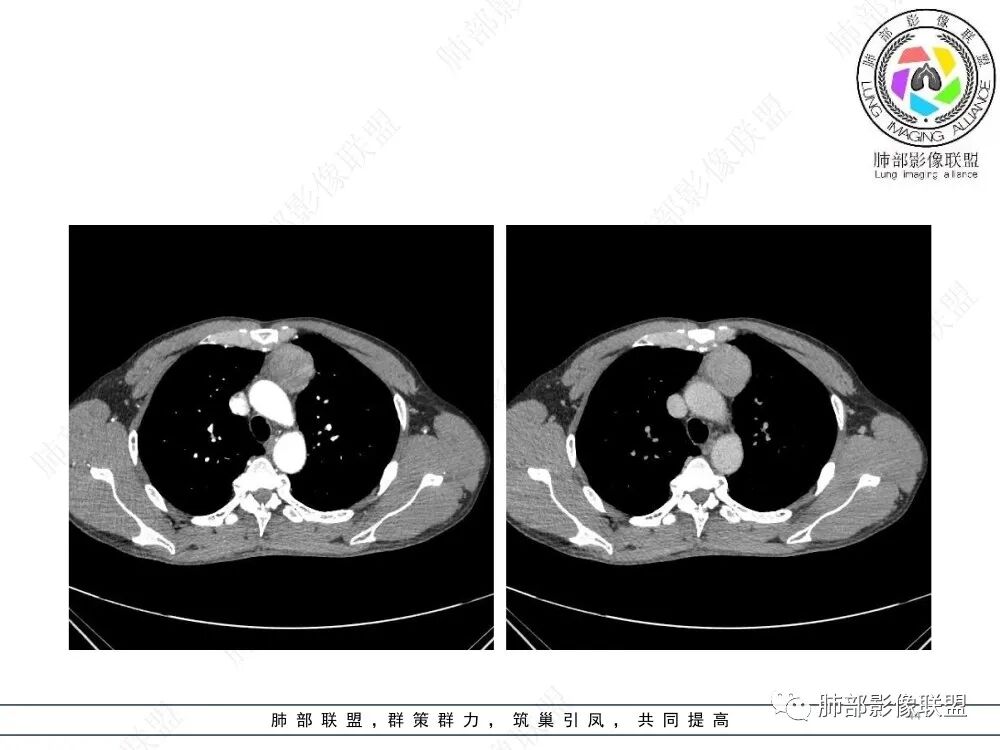

放射小白:男性47岁,前纵隔团块状占位,边界尚清,增强中度强化,内部疑似纤维分隔,常规考虑胸腺瘤可能(A/AB型),鉴别类癌、CD。

瑞欣:中年男性,检验未见明显异常,前纵隔软组织快影,边界清,可见明显强化,首先考虑胸腺瘤,鉴别淋巴瘤,畸胎瘤,生殖细胞瘤。

金豆:晨读:定位前纵隔,膨胀性生长,质地中等,边界清,有浅分叶,中等强化,似乎有裂隙低密度,常规胸腺瘤(B1)。

Yishion:晨读:纵隔占位,偏侧生长,边界清楚,有浅分叶,强化明显,其内似见纤维分隔,常规考虑胸腺瘤(AB型)。

蓝天白云:晨读:47岁男,前纵隔占位,边界清,有浅分叶,中等强化,胸腺瘤(B1)。

宇宙:前纵膈偏左类圆形肿块,边界清晰光整,与大血管脂肪间隙清,密度均匀,轻中度强化,考虑胸腺瘤,A型?鉴别胸腺癌。

玫:男,47岁,咳嗽,咳痰一年,前纵隔软组织密度肿块影,边界清晰,内密度均匀,增强扫描轻度强化,考虑胸腺瘤可能。

周太狼:中年男性,前上纵隔胸腺区软组织团块占位,边界清,增强中度强化,内密度较均匀,常规考虑胸腺瘤。

月亮圆了!:前纵隔包块,边界清,有分叶,密度不均,中等强化,考虑胸腺瘤。

衡妈🇨🇳:中年男性,前纵隔偏左侧实性占位,密度相对均匀,边缘分叶,周围脂肪结构略模糊,增强后动脉期不均匀强化,有低密度区,纤维分隔显示不清。考虑胸腺瘤B1 B2型。

朱伟超:中年男性,前纵膈偏离中线肿块,浅分叶,内有分隔,中等不均匀强化,常规胸腺瘤。

流心明智:男,47,咳嗽、咳痰1年余。胸部CT:前纵膈偏左类圆形肿块,瘤肺界面清晰光整,纵隔侧部分层面絮状影?平扫密度较均匀,增强后轻度强化,内可见宽带及线样低密度分隔。邻近左上肺受压凹陷。考虑胸腺肿瘤,AB型?胸腺Ca?鉴别淋巴瘤、N源性肿瘤、CD等。

2、影像特点:前纵隔偏左侧软组织影,密度相对均匀,未见明显包膜钙化及实质内钙化,局部边缘浅分叶,周围脂肪间隙密度增高、浑浊,未见侵犯大血管、未见纵隔内淋巴结转移、未见侵犯心包内结构、未见胸膜转移结节、未见肿块沿着纵隔胸膜蔓延,未见胸腔积液。增强后动脉期不均匀强化,未见明显纤维分隔。